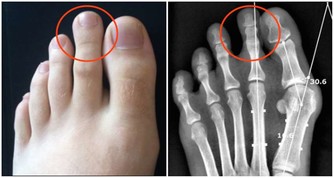

6、 遺傳因素也是一方面,痛風是一種遺傳代謝性疾病,具有遺傳性。患有痛風病的家族裡,如果不調節自己的飲食習慣,就很容易患上痛風。因為體內缺少一種酶,就不能把蛋白質分解。最後結晶成小晶體堆積在關節內,誘發疾病。

根據調查顯示:痛風患者的初發平均年齡在不到20年的時間裡下降了6.3歲,開始襲擊年輕人。據分析發現,痛風的初次發病年齡有明顯年輕化的趨勢,不足40歲的初次發病者增加了26.3%。

年輕人患痛風的原因是什麼呢?專家認為,攝入富含嘌呤類食物(含有嘌呤代謝紊亂的食物如動物內臟,魚蝦蛋白以及啤酒等,肝,腎,肉餡,肉汁,肉湯,鯖魚,風尾魚,沙丁魚,魚卵,小蝦,淡菜,鵝,斑雞,石雞等含嘌呤都很高,再者熏火腿,豬肉,牛肉,兔肉,鴨,鴿,貝殼類含嘌呤也是比較高的,如果有痛風就不建議吃這些食物。)者迅速增多是主要原因。人們的飲食結構已經發生了明顯的變化,尤其是20歲至40歲的年輕人飲食中含高能量、高嘌呤類物質者顯著增加。數據顯示:20歲至40歲年齡組的痛風病人發病前,90%以上有經常大量飲酒和嗜好吃肉、動物內臟、海鮮等富含嘌呤類成分食物的習慣。